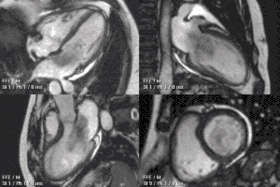

عملکرد قلب با استفاده از تصویربرداری ساین

اطلاعات عملکردی و ساختاری با استفاده از توالی ساین bSSFP بدست میآید. اینها معمولاً به صورت گذشته نگر و دارای کانتراست بسیار بالایی در تصویربرداری قلبی به دلیل نسبت نسبتاً زیاد T2: T1 خون در مقایسه با میوکارد هستند. تصاویر معمولاً برای دستیابی به طرحهای استاندارد قلبی که برای ارزیابی مورد استفاده قرار میگیرند، به صورت پی در پی برنامهریزی شدهاند. جریان پر تلاطم باعث برهم خوردن فاز میشود و از دست دادن سیگنال به بیماری دریچه ای اجازه قدردانی کیفی میدهد. ساینهای محور کوتاه بطن چپ از پایه به سمت حداکثر حفره بدست میآیند و برای کمی کردن حجمهای پایان دیاستولیک و سیستولیک انتهایی، و همچنین توده میوکارد استفاده میشود. توالی برچسب زدن الگوی شبکه که با انقباض قلبی تغییر شکل میدهد را تحریک میکند و باعث کرنش میشود.

نقص دیواره بین دهلیزی با اتساع بطن راست توسط CMR

تخلیه وریدی ریوی غیرعادی جزئی توسط CMR

بطن راست بزرگ شده با عملکرد ضعیف در بیمار با ترتالوژی ترمیم شده از Fallot توسط CMR